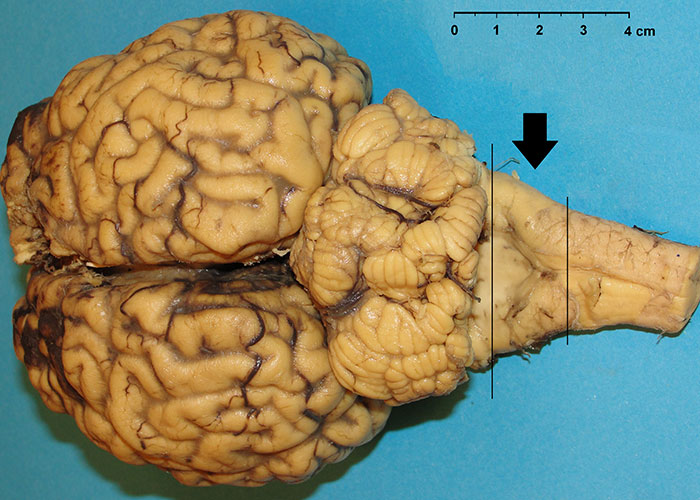

Histological examination needs to be performed on formalin-fixed, paraffin embedded brain sections that are stained with haematoxylin and eosin (H&E). The classic histological changes in the CNS that are visible microscopically are vacuolation of grey matter neuropil (spongiform change) and/or vacuolation of neurons, with a predilection for certain neuroanatomic locations; astrocytosis and neuronal degeneration may also be present.102 Vacuolation of the perikaryon and spongiform changes are usually bilaterally symmetrical.118 A single coronal section of the medulla oblongata at the level of the obex (Figure 5) was identified as appropriate for the histopathological diagnosis of BSE because the vast majority of cases have vacuolar changes in either the solitary tract nucleus NST, (Figure 6) or spinal tract nucleus of the trigeminal nerve (NSTV) although in a small proportion of cases vacuolar changes may be minimal.115 Cases detected by monitoring healthy slaughter cattle in abattoirs, however, may not present with any vacuolar changes at all in these nuclei.104